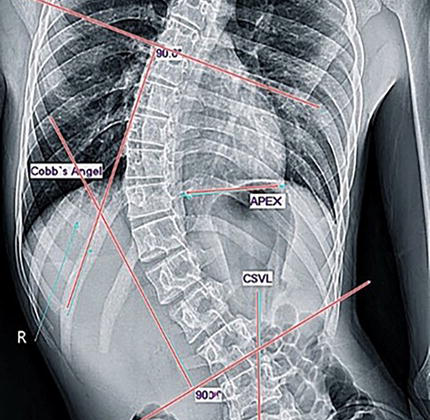

كيف يتم اكتشاف الجنف (اعوجاج العمود الفقري) مبكرًا؟

عادة يتم التشخيص من خلال:

- الفحص السريري للظهر

- الأشعة السينية للعمود الفقري

- متابعة الحوض وتوازن الجسم

- في بعض الحالات: تصوير متقدم لتقييم العظام